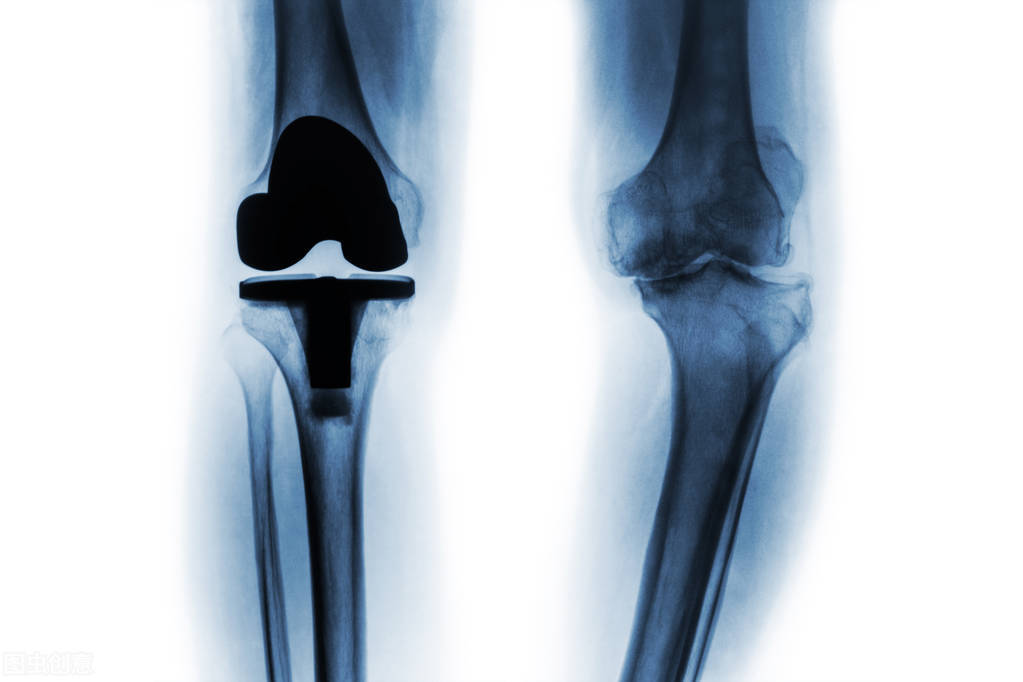

人工关节集采平均降价82% 拟中选髋关节、膝关节均价从万元时代进入千元时代

备受关注的国家组织人工关节集中带量采购昨天产生拟中选结果,拟中选髋关节平均价格从3.5万元下降至7000元左右,膝关节平均价格从3.2万元下降至5000元左右,平均降价82%。

本次采购产品范围为人工髋关节、人工膝关节,首年意向采购量共54万套,占全国医疗机构总需求量的90%。按2020年采购价计算,公立医疗机构人工髋、膝关节采购金额约200亿元,占高值医用耗材市场的10%以上。共有48家企业参与本次集采,44家中选,中选率92%。内外资企业均有产品拟中选,既包括医疗机构常用的知名企业,也包括新兴企业,兼顾了市场稳定性和活力。